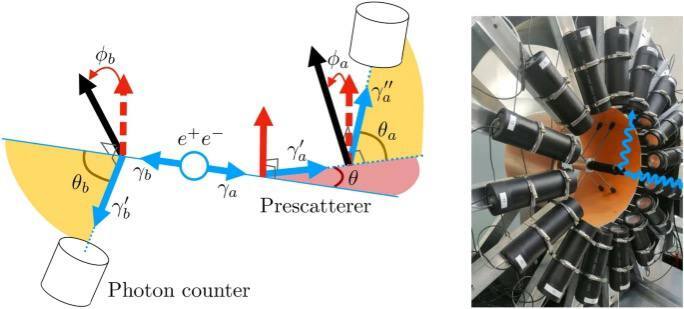

Эти метки начинают испускать позитроны (анти-электроны). Те сталкиваются с электронами в тканях и аннигилируют — то есть исчезают во вспышке энергии. От такого рождаются два гамма-фотона, вылетающие строго в противоположные стороны.

Детекторы томографа ловят эти фотоны и по точкам их прихода строят 3D-карту. Где ярче — там и подозрительная активность, потенциальная опухоль.

Дело в том, что тело человека — не вакуум. Эти гамма-фотоны, прежде чем долететь до детектора, ныряют в ткани, сталкиваются с атомами... Это называется комптоновское рассеяние.

В итоге детектор ловит кучу фотонов, которые сбились с пути, потеряли часть энергии и летят не туда, куда должны. Это — мусорные события. Шум. Он забивает полезный сигнал, делает картинку нечёткой, и в итоге врач может увидеть не чёткую опухоль, а какое-то невнятное пятно.

Группа учёных из МФТИ и Института ядерных исследований РАН решила проверить эту аксиому на своей уникальной установке. Они взяли пары запутанных гамма-фотонов, рождённых при аннигиляции (как в реальном ПЭТ), и начали их намеренно расшвыривать под разными углами — моделировали то самое комптоновское рассеяние, которое и портит картинку в томографе.

Ожидалось, что рассеяние — это мгновенная потеря запутанности. Но результаты (кстати, опубликованные в Scientific Reports), как говорится, поразили.

Оказалось, что старая догма — чушь. Запутанность сохранялась. Практически полностью. Даже после серьёзного рассеяния! Фотоны, прошедшие через разные взаимодействия, всё ещё оставались связаны этой невидимой квантовой нитью со своими напарниками.